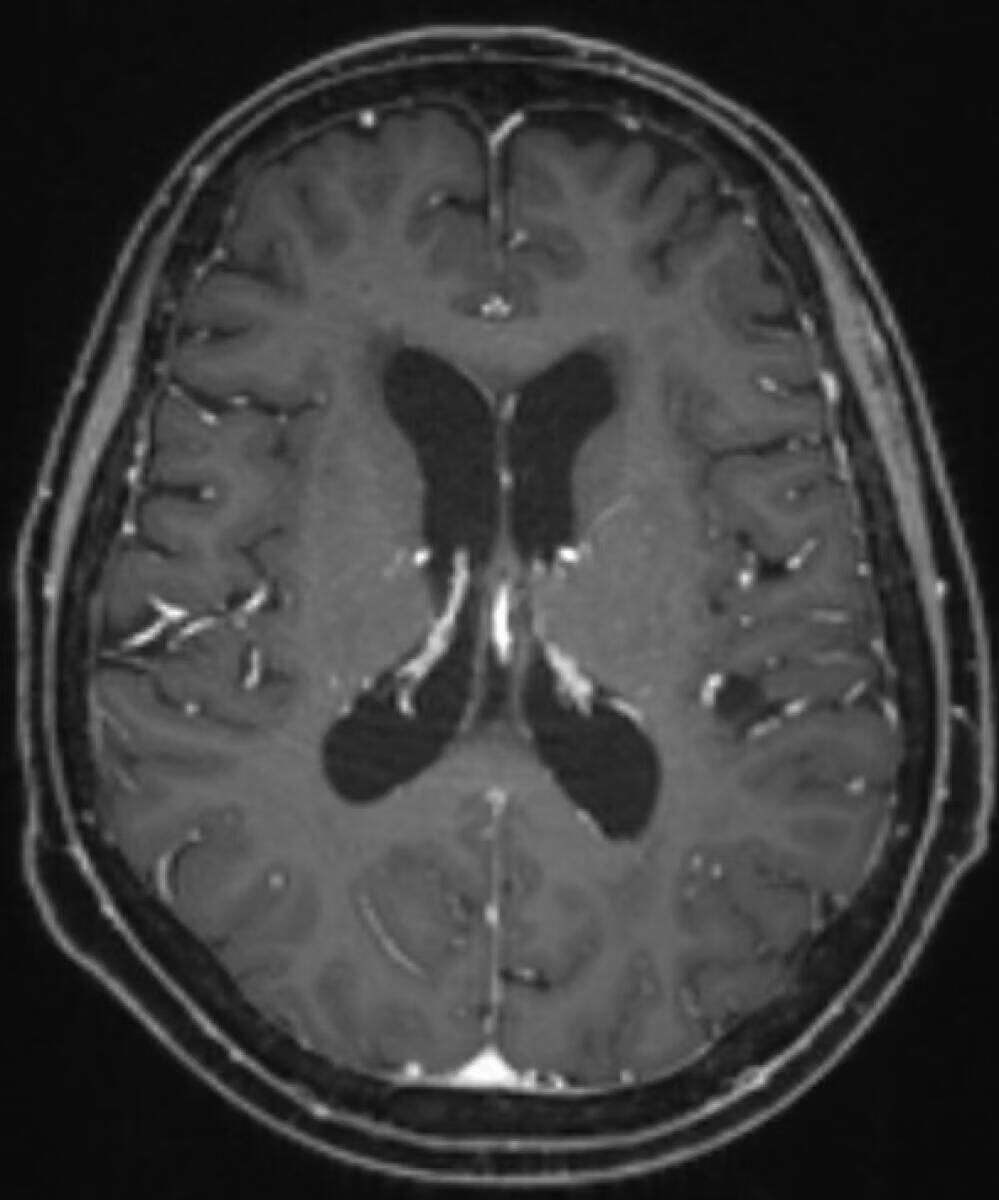

肺腺伴脑转移,放化疗后一直单线奥西,12月初复查头颅新增病灶较前增大,考虑有脑膜转移,目前偶尔头晕,头痛,持续时间短(自确诊以来偶尔都有),本地医生建议双倍奥西,现已经口服双倍20多天,请问没有症状的脑膜转移需要鞘注吗?脑膜转移可逆吗?有没有可能双倍奥西后脑膜转移就消失,病灶缩小了?求各位大佬指导